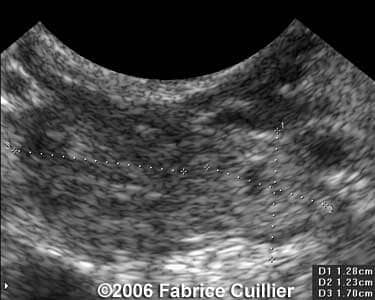

These are some cases of ectopic pregnancy (GEU) using the 2D and 3D scans.

Case 4